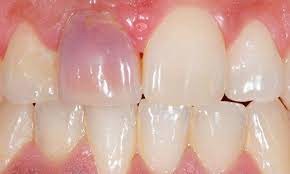

You have seen smiles that you know have dental crowns in the front. You look at them and say to yourself that something is not natural. Many times, it is the dark rim of gum tissue that gives it away. The dark rim of gum tissue does not occur around natural teeth, only around teeth that have been covered with dental crowns.

The dark line is associated with an old porcelain dental crown. This style of dental crown is referred to as a porcelain fused-to-metal dental crown because it uses tooth-colored porcelain on the outside and it uses metal under the porcelain for strength. The dark line originates from the edge of the dental crowns where the porcelain and the metal meet at a knife-edge at the gum line. At the knife-edge, a very thin amount of the metal always shows. One of the illusionary techniques cosmetic dentists have used was to hide the thin dark line under the gum line. Over time, the gum tissue would recede and expose the dark line. In some patients the dark line would show through the gum and make it appear dark as well.

How Do You Get Rid of It?

The only way to eliminate the esthetic problem is to replace the dental crowns. When replacing just one single dental crown in the front, you should expect that it might take more than one try-in of the new dental crown before it is permanently cemented into place. Because your central incisors are the most prominent teeth in the mouth, matching them is the most difficult esthetic challenge. Only the best dental technicians are able to mimic one central incisor tooth next to another.

What Are Some of the Replacement Dental Crowns Like?

Some of the clever ways dentists and dental technicians have been able to mimic natural teeth is through the new advancements in dental materials. New all-tooth-colored ceramic dental crowns are the latest technological advancement cosmetic dentists have to recreate natural teeth. In comparison to porcelain fused-to-metal dental crowns, all-ceramic dental crowns do not contain any metal, thus no dark line can appear.